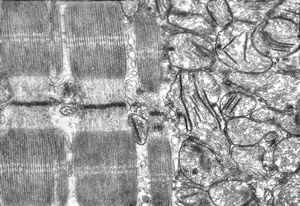

rat | skeletal muscle 6h. post ex. … changes of mitochondrial cristae